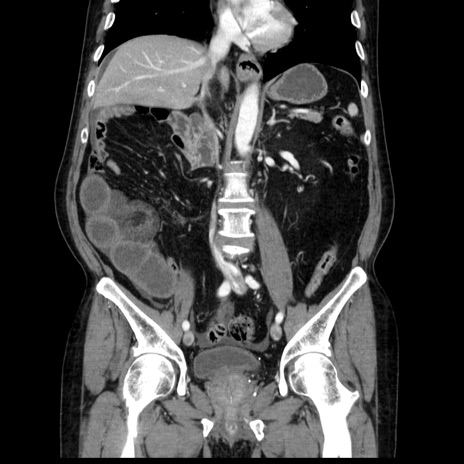

症例30(冠状断像)

【症例】80歳代男性

【主訴】臍周囲痛

【現病歴】約6時間前から臍下部痛が出現。次第に腹部膨隆・背部痛も生じてきたため来院。背部痛の場所は変化しない。

【身体所見】意識清明、BT 36.3℃、BP  131/87mmHg、P 87bpm、SpO2 100%(RA)、臍周囲自発痛・圧痛あり、反跳痛なし、自発痛部位に一致して板状硬あり、腹部膨隆、腸雑音減弱、CVA tenderness両側陰性。

【データ】WBC 19600、CRP 0.33